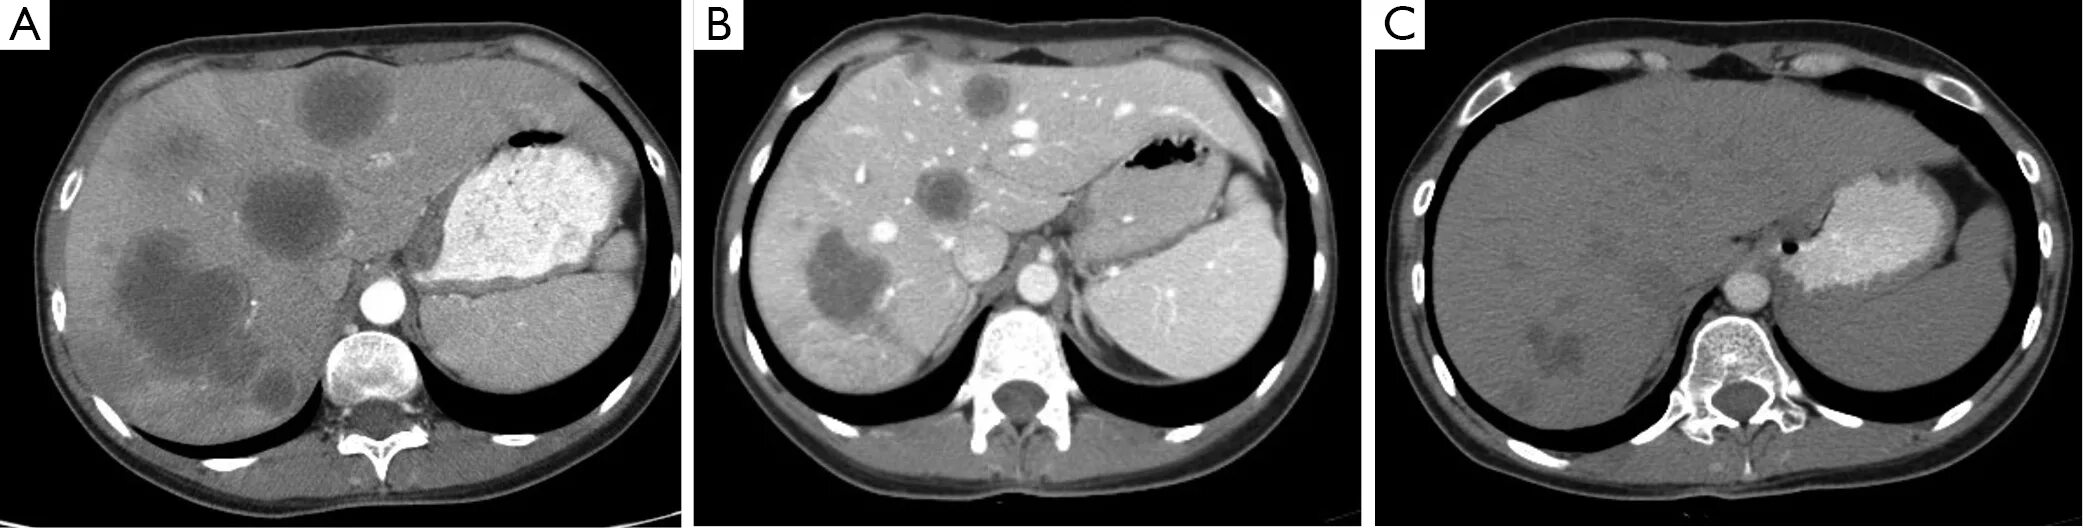

3 метастазы в печени